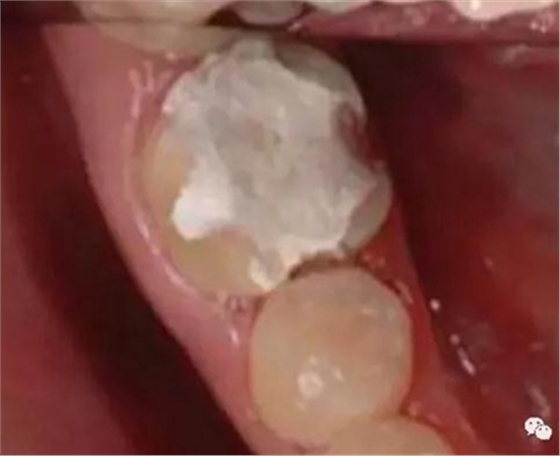

箱型固位形

3.基牙具有良好的抗力形

保留較多的牙體組織

增加牙體抗力形的措施